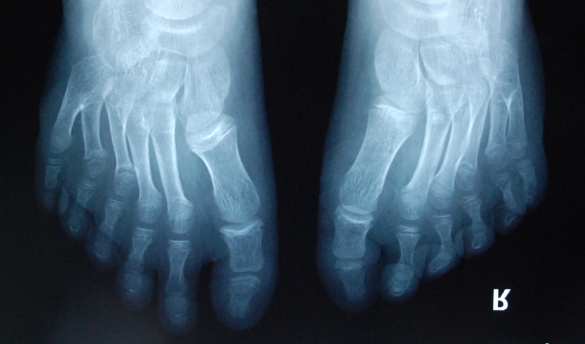

廈門眼科中心小兒眼科修陽暉博士在日常的診療過程中就接診了不少這樣的的特殊家庭,讓其尤為印象深刻的就是一年前接診的BBS綜合征患者。當(dāng)時(shí)來院就診的是一對親兄弟,之前已在多家醫(yī)院做過檢查,因其均有較大散光和斜視,肉眼下眼底檢查未見異常,故外院均診斷為弱視,這也符合眼科門診常規(guī)的診斷邏輯與思維。但由于兄弟倆均有智力發(fā)育遲緩、特殊面容及四肢均有六指和六趾的特異體征引起了修陽暉博士的警覺:會(huì)不會(huì)是一種特殊遺傳性疾病或綜合征?后續(xù)的檢查結(jié)果進(jìn)一步證實(shí)了修陽暉博士的懷疑---患兒均有夜盲,ERG、VEP及OCT檢查顯示雙眼的視網(wǎng)膜神經(jīng)上皮層結(jié)構(gòu)及功能均明顯異常。由于之前未遇到此種病例,修陽暉博士在診斷一欄寫下視網(wǎng)膜色素變性并打上了個(gè)問號,同時(shí)留下了病人的聯(lián)系方式。

BBS綜合征(Bardet-Biedl綜合征)是一種主要累及纖毛結(jié)構(gòu)與功能的罕見常染色體隱性遺傳性疾病。纖毛分布于哺乳動(dòng)物體內(nèi)的大多數(shù)細(xì)胞,它是一種廣泛存在于各種細(xì)胞表面的細(xì)胞器,體型微小但結(jié)構(gòu)復(fù)雜、作用強(qiáng)大,能感知細(xì)胞外機(jī)械和化學(xué)信號變化并協(xié)助其轉(zhuǎn)導(dǎo)到細(xì)胞內(nèi)部從而引起細(xì)胞應(yīng)答。高等動(dòng)物的視覺、觸覺、嗅覺、聽覺的傳遞都依賴于體內(nèi)外正常的纖毛結(jié)構(gòu)和功能。因此BBS綜合征常累及全身多個(gè)系統(tǒng)和器官,在臨床上主要表現(xiàn)為:視網(wǎng)膜色素變性、智力發(fā)育異常、向心性肥胖、多指(趾)、性腺發(fā)育異常、腎臟異常。除此之外還有許多諸如:語言發(fā)育障礙、聽力異常、嗅覺異常、斜視、白內(nèi)障、散光、牙齒發(fā)育異常、短指(趾)、并指(趾)、肝纖維化、糖尿病、高血壓等表現(xiàn)。